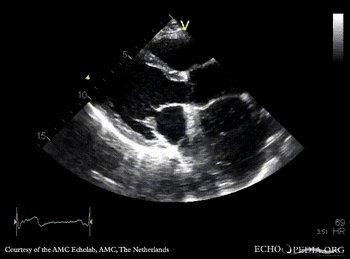

| A4CH | A4CH color doppler |